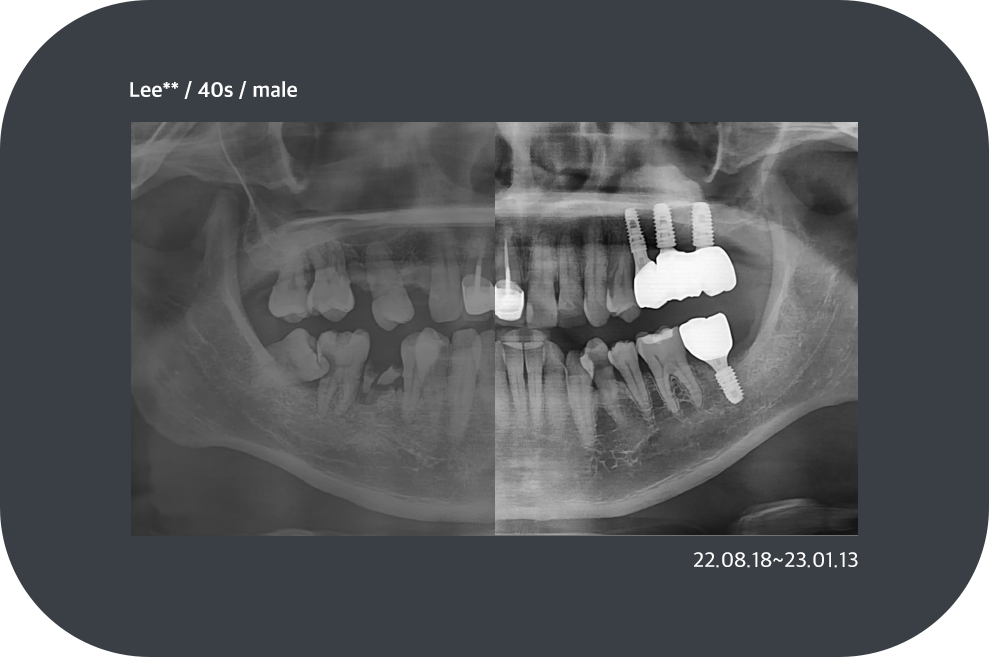

치료사례

임플란트 치료사례

*모든 증례 사진은 의료법 제23조, 제56조에 의거하여, 당사자의 동의하에 게시하였습니다.

*치료 사진은 모두 본원에서 치료한 환자분의 사진입니다.

*치료 사진은 모두 동일인의 사진이며, 동일조건에서 촬영하였습니다.

*개인의 차이에 따라 시술 및 수술 후 부작용이 발생할 수 있으며, 의료진과 충분한 상담을 받으시기 바랍니다.